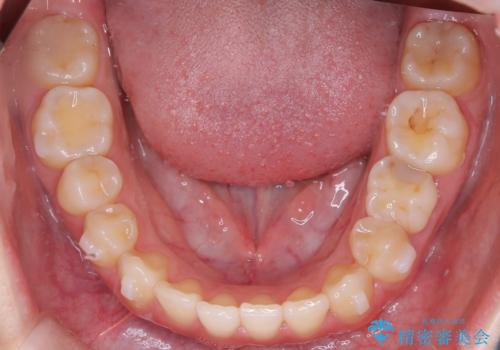

- 前歯の捻れを主訴に来院されました。

インビザラインを希望されておりましたが、20時間もつけることができなかったためワイヤー矯正にて叢生の改善を行っています。

右上の側切歯(前から2番目の歯)が90度程度ねじれている状態でしたが、1月に1回のワイヤー交換できれいに並ぶことができ満足いただけました。

捻れた歯の治療に関しては、ワイヤー矯正の方が仕上がりがきれいに治りやすいです。